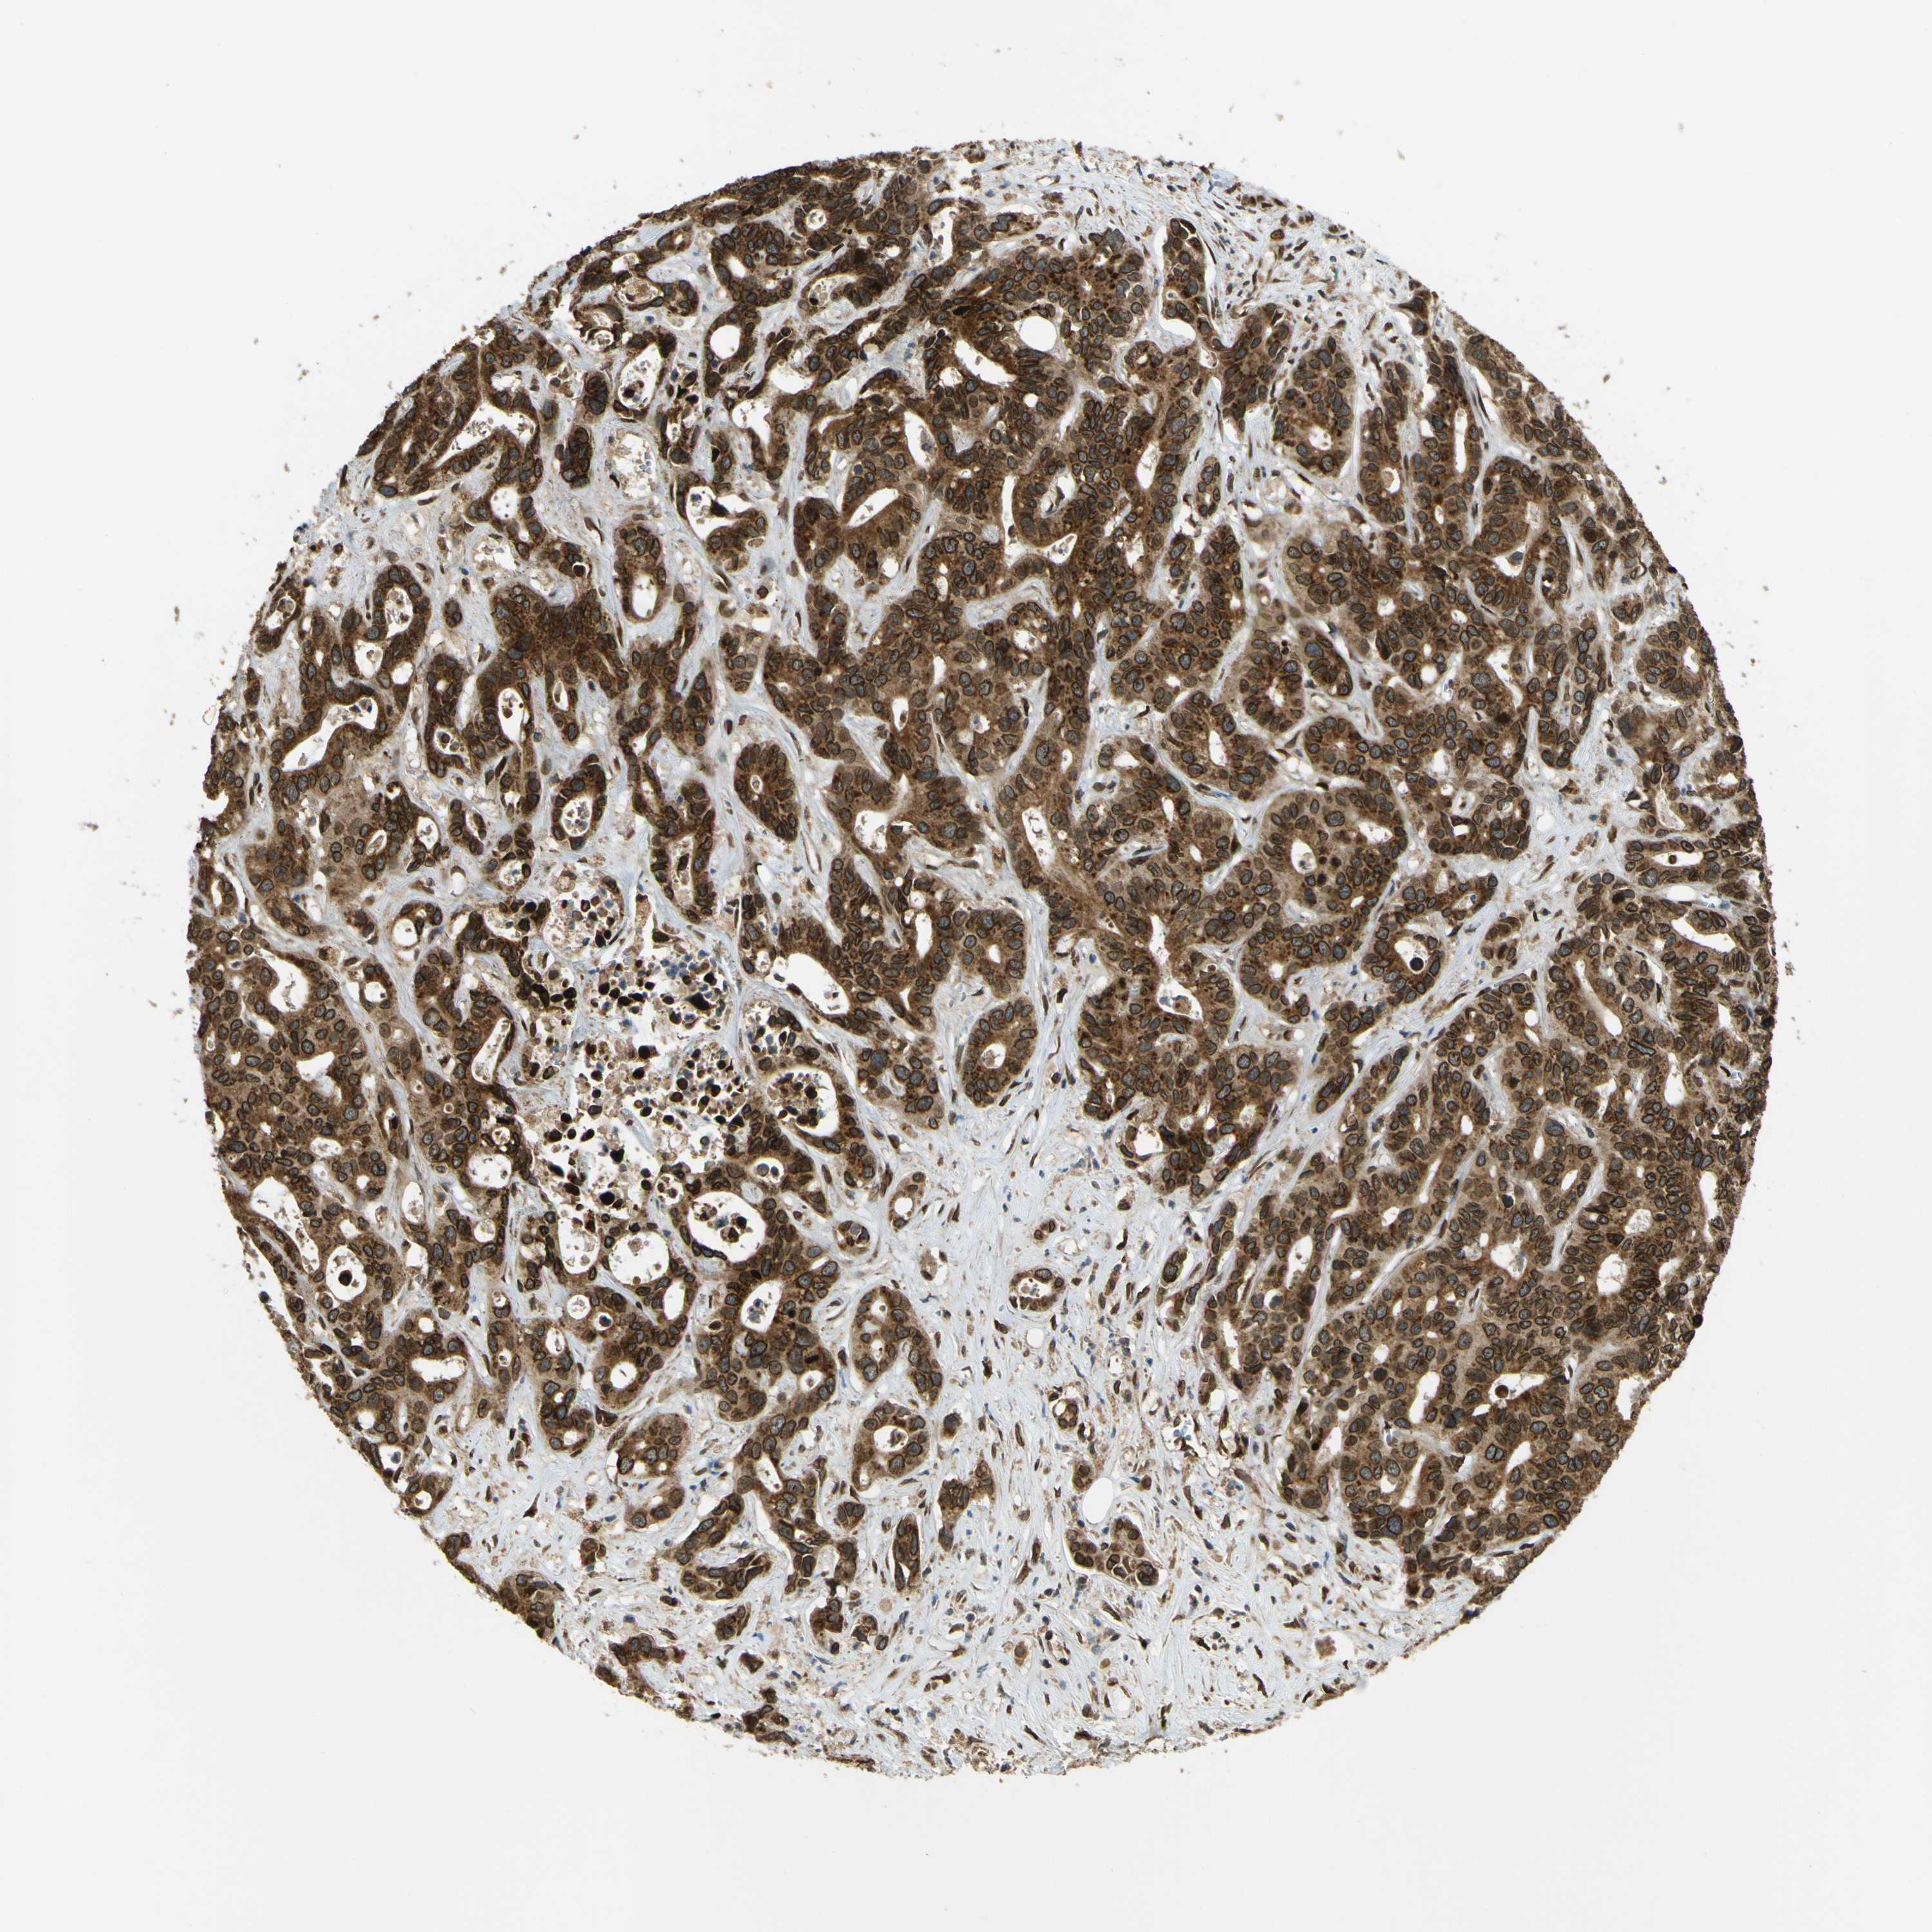

LIVER CANCER - Protein expressioni

A mouse-over function shows sample information and annotation data. Click on an image to view it in a full screen mode. Samples can be filtered based on level of antibody staining by selecting one or several of the following categories: high, medium, low and not detected. The assay and annotation is described here.

Note that samples used for immunohistochemistry by the Human Protein Atlas do not correspond to samples in the TCGA dataset.

Antibody stainingi

Antibody staining in the annotated cell types in the current human tissue is reported as not detected, low, medium, or high, based on conventional immunohistochemistry profiling in selected tissues. This score is based on the combination of the staining intensity and fraction of stained cells.

Each image is clickable and will lead to virtual microscopy that enables deeper exploration of all samples and also displays staining intensity scores, fraction scores and subcellular localization as well as patient and tissue information for each sample.

Antibody HPA012628

Staining

High

Medium

Low

Not detected

Intensity

Strong

Moderate

Weak

Negative

Quantity

>75%

75%-25%

<25%

None

Location

Nuclear

Cytoplasmic/membranous

Cytoplasmic/membranous,nuclear

Cholangiocarcinoma

Carcinoma, Hepatocellular, NOS